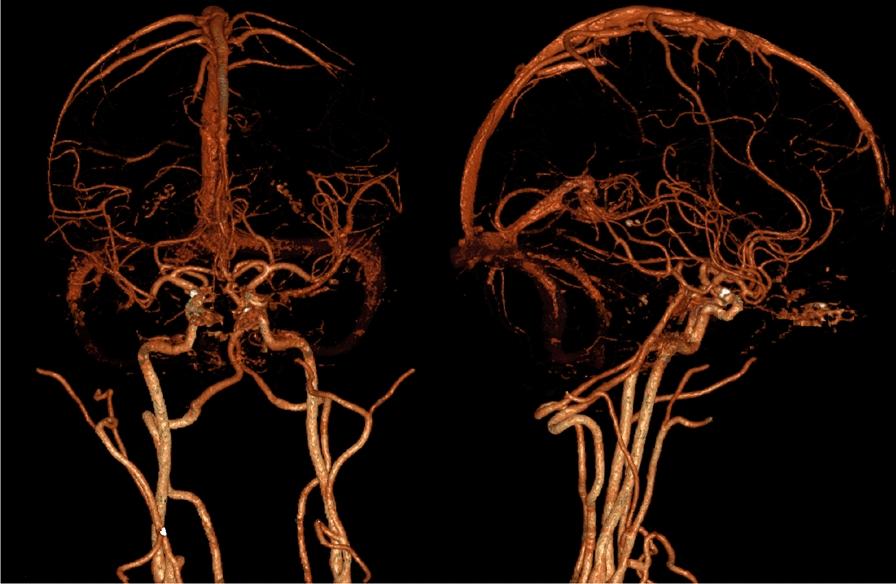

In this paper, we present two White male patients of Central European (Polish) descent (50 and 64 years old) who, although reported to have had acute ST-elevation myocardial infarction, turned out to be ST-elevation myocardial infarction latecomers. In both cases, we were dealing with the presence of left ventricular thrombus and complications related to the central nervous system. On the basis of these two patients, we discuss the role of revascularization in latecomer ST-elevation myocardial infarction patients. We present the position of direct oral anticoagulants in the left ventricular thrombus treatment and show that, in limited cases of a huge thrombus, cardiac surgery is a treatment of choice.

在本文中,我们介绍了两名中欧(波兰)血统的白人男性患者(分别为50岁和64岁),他们虽被报告患有急性ST段抬高型心肌梗死,但实际上是ST段抬高型心肌梗死的延迟就诊者。在这两个病例中,均存在左心室血栓以及与中枢神经系统相关的并发症。基于这两名患者,我们讨论了血运重建在延迟就诊的ST段抬高型心肌梗死患者中的作用。我们阐述了直接口服抗凝剂在左心室血栓治疗中的地位,并表明在巨大血栓的有限病例中,心脏手术是首选治疗方法。